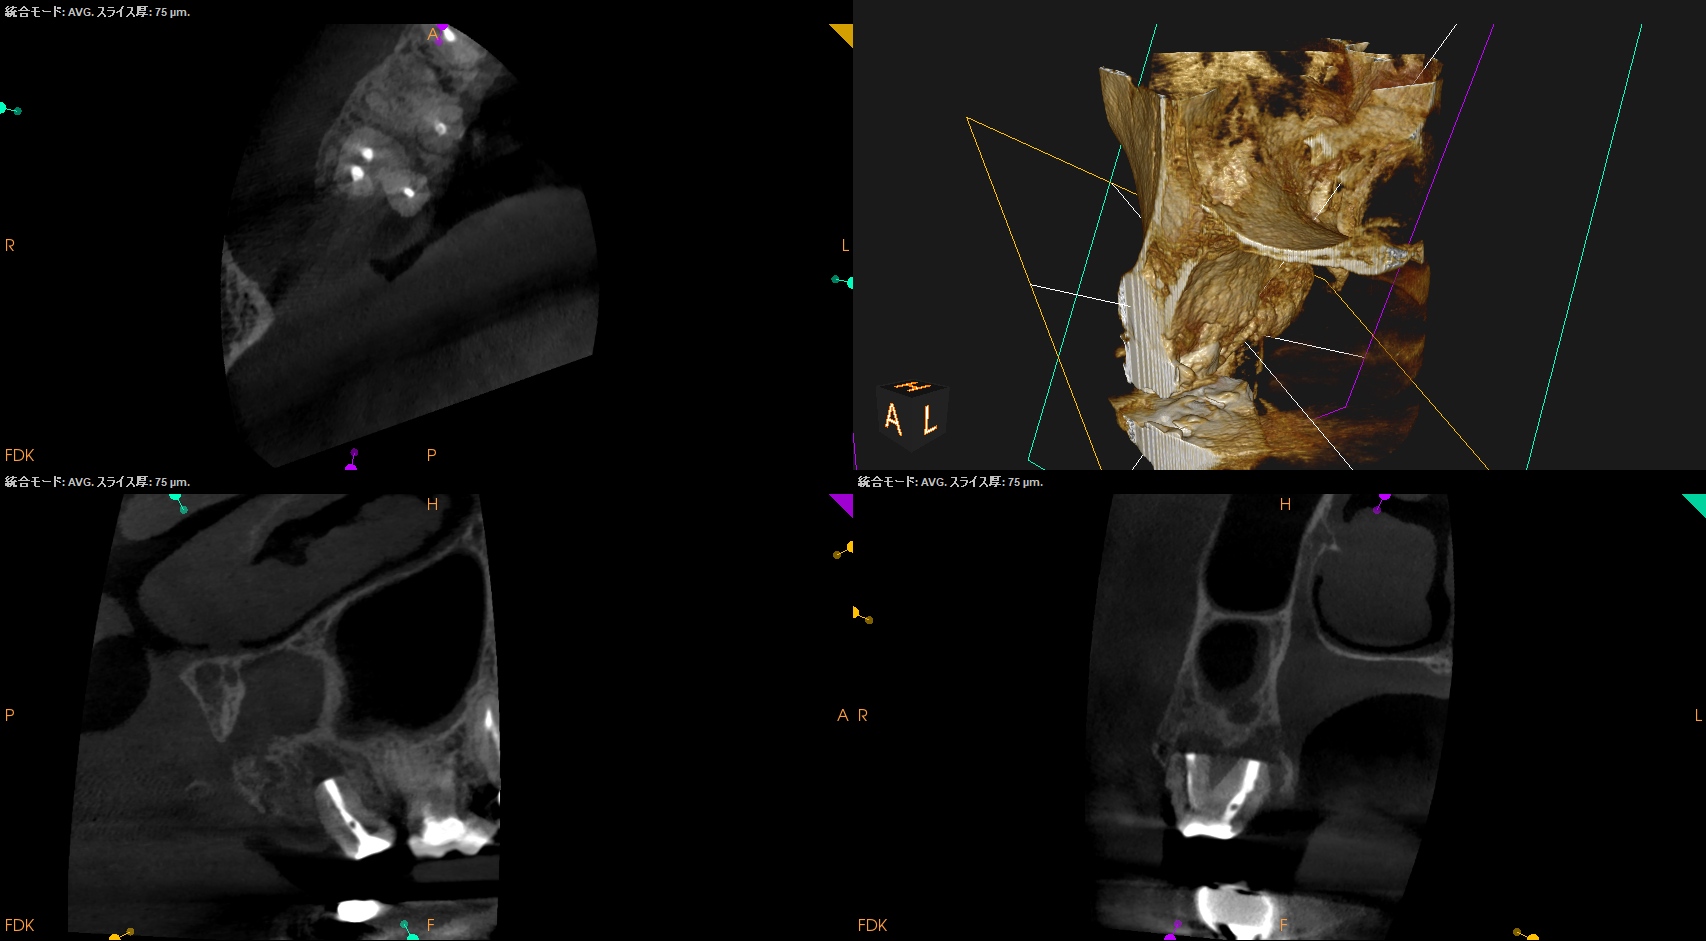

以前の治療の経過観察。

あれからさらに1ヶ月が経過した。

#2 Intentional Replantation 2M recall(2025.10.1)

痛みはないが若干、違和感がある程度に症状は軽減した。

臨床症状はないのでかかりつけ医の先生にはプロビジョナルレストレーションの装着を依頼した。

次回はさらに4ヶ月後の術後・半年後である。